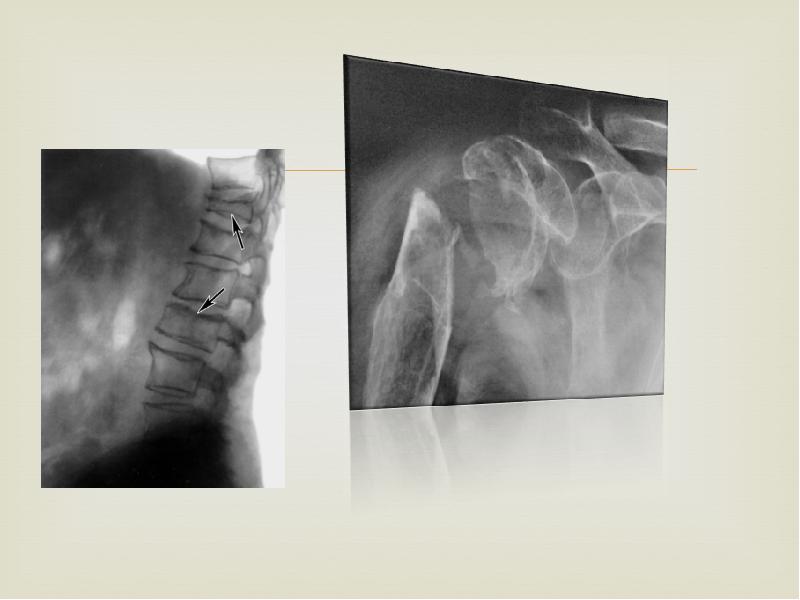

Остеопороз является одним из более поздних тяжелых осложнений. Проявляется он болями в костях, нередко очень интенсивными. Остеопороз всегда генерализованный, но его интенсивность, выявляемая рентгенологически, обычно неравномерная. Наиболее часто рентгенологически выявляется остеопороз позвоночника, ребер, костей черепа, таза, реже ключиц и особенно редко длинных трубчатых костей. Могут быть «патологические» переломы, чаще позвоночника, ребер, неадекватные интенсивности травмы.